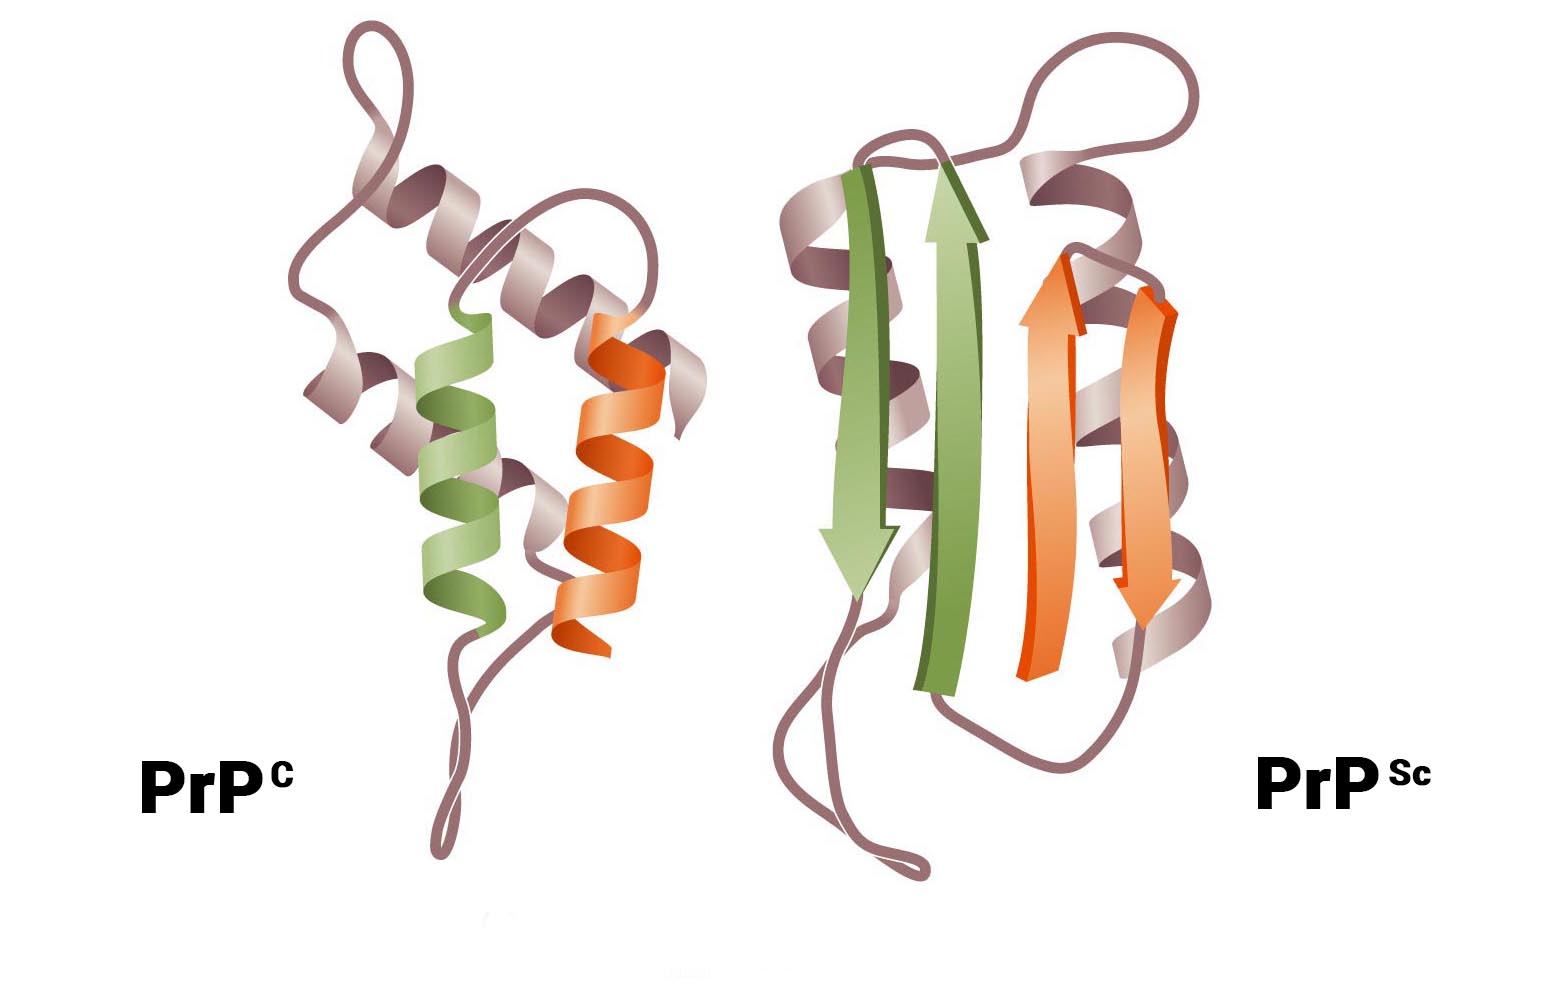

В ходе исследований было установлено, что возбудитель прионных заболеваний – мутированная (инфекционная) форма низкомолекулярного белка, названного прионным протеином (PrP). Прион (от англ. Proteinaceous infection particle) – белковоподобная инфекционная частица. Нормальная спиралевидная форма прионного протеина PrPС обнаружена в организме всех млекопитающих, в том числе и человека. Её кодирует единственный ген под названием PRNP, высокие уровни устойчивой экспрессии которого обнаруживают в нейронах в пятьдесят раз чаще, чем в глии.

Развитие болезни может происходить как за счёт точечных мутаций, так и в результате рекомбинантных событий. Мутации гена, кодирующего PrPС, программирует выработку другой, мутированной плоской формы – PrPSc с изменёнными аминокислотами. Таким образом, образование инфекционных прионовых белков происходит не за счёт репродукции молекулы PrPSc, попавшей в организм, а за счёт синтеза новых молекул, кодируемых мутировавшим геном PrPС.

Позже появились другие теории. Так, согласно одной из них, причина инфекционности PrPSc в следующем: инфекционный прион является зародышем для цепочечной полимеризации нормальных прионов. Конверсия PrPС в PrPSc представляет собой посттрансляционный процесс, включающий глубокое конформационное изменение, являющееся фундаментальным событием, лежащим в основе размножения инфекционных прионов. Эта форма обнаружена в организме людей и животных, больных прионными заболеваниями – трансмиссивными спонгиоформными (губкообразными) энцефалопатиями. В 1997 году за это открытие С. Прузинеру была вручена Нобелевская премия. Таким образом, установлено, что инфекционным агентом болезни Кройтцфельдта-Якоба, куру и скрепи служит белок.

Патогенез поражения обусловлен мутацией гена, кодирующего PrPС, программирующего выработку другой, мутированной, плоской формы – PrPSc с изменёнными аминокислотами. В другом случае конверсия PrPС в PrPSc представляет собой посттрансляционный процесс, включающий глубокое конформационное изменение, являющееся фундаментальным событием, лежащим в основе размножения инфекционных прионов. Молекула PrPSc соединяется с молекулой PrPС с образованием димерного продукта, трансформирующегося с двумя молекулами PrPSc. В следующем цикле две молекулы PrPС соединяются с двумя молекулами PrPSc, что обеспечивает экспоненциальное образование молекул PrPSc. Белок PrPС – короткоживущий (период полураспада 5 – 6 часов), растворимый в жидких средах организма.

В противоположность этому инфекционный белок PrPSc накапливается в цитоплазменных везикулах, что приводит к последующему нарушению функции синапсов и развитию глубоких неврологических дефектов. Позднее PrPSc высвобождается во внеклеточное пространство и откладывается в виде амилоидных бляшек. PrPSc форма обнаружена в организме людей и животных, больных прионными заболеваниями – трансмиссивными спонгиоформными (губкообразными) энцефалопатиями.